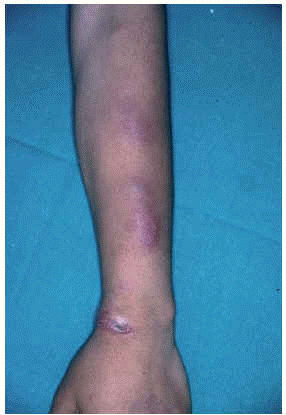

Los casos diseminados se suelen dar en pacientes inmunodeprimidos con infecciones por M. avium-intracellulare, M. kansasii, M. abscessus y M. chelonae. Desde el punto de vista dermatológico, existen multitud de formas de presentación como pápulas, placas, nódulos, abscesos, etc. (figs. 6 y 7). Algunas micobacterias atípicas adoptan ciertos patrones morfológicos en cuanto a su distribución corporal. De esta forma, el patrón esporotricoide es más frecuente en M. marinum y M. kansasii siendo poco frecuente en el M. chelonae59,60.

Fig. 6.--Úlcera en región pretibial por M. chelonae.

Fig. 7.--Nódulos y fístulas de drenaje por M. chelonae.

El periodo de incubación oscila entre 3 semanas y 6 meses111. La principal presentación cutánea es la forma diseminada con 5-100 nódulos eritematosos circunscritos o con tendencia a confluir en grandes masas con fístulas de drenaje múltiples100 (figs. 15A y B y 16). También se puede presentar como nódulos subcutáneos simulando lesiones vasculíticas128. Se suelen localizar en las regiones dorsales de las extremidades100. Preferentemente afectan las extremidades inferiores129 y deberían entrar en el diagnóstico diferencial de los procesos que cursan con nódulos crónicos en dicha localización119 (fig. 17). No suelen tener disposición lineal ni esporotricoide. Las lesiones de mayor tamaño pueden ser dolorosas y son raros los síntomas sistémicos. En excepcionales ocasiones puede precederse de afectación pulmonar130 o de fiebre periódica131. La segunda forma de presentación, en orden de frecuencia, son las celulitis localizadas, los abscesos subcutáneos o la osteomielitis. La tercera forma es la relacionada con el uso de catéteres100.

Figs. 15A y B.--Nódulos por M. chelonae en extremidades inferiores.

Fig. 16.--Detalle de la anterior.

Fig. 17.--Lesiones en extremidades inferiores por M. chelonae.